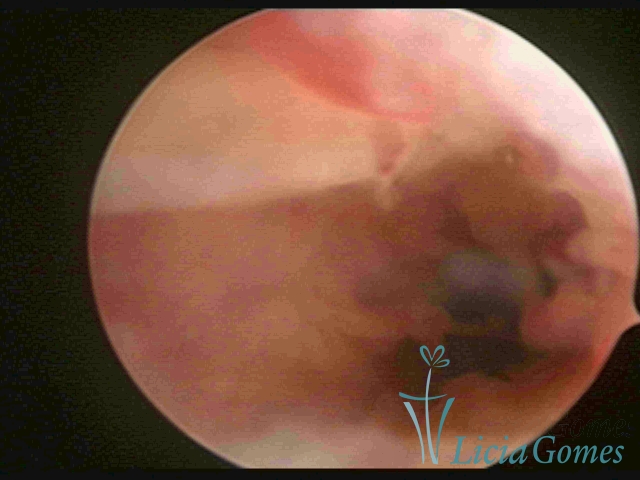

Canal cervical trófico, com o fio de Mirena®